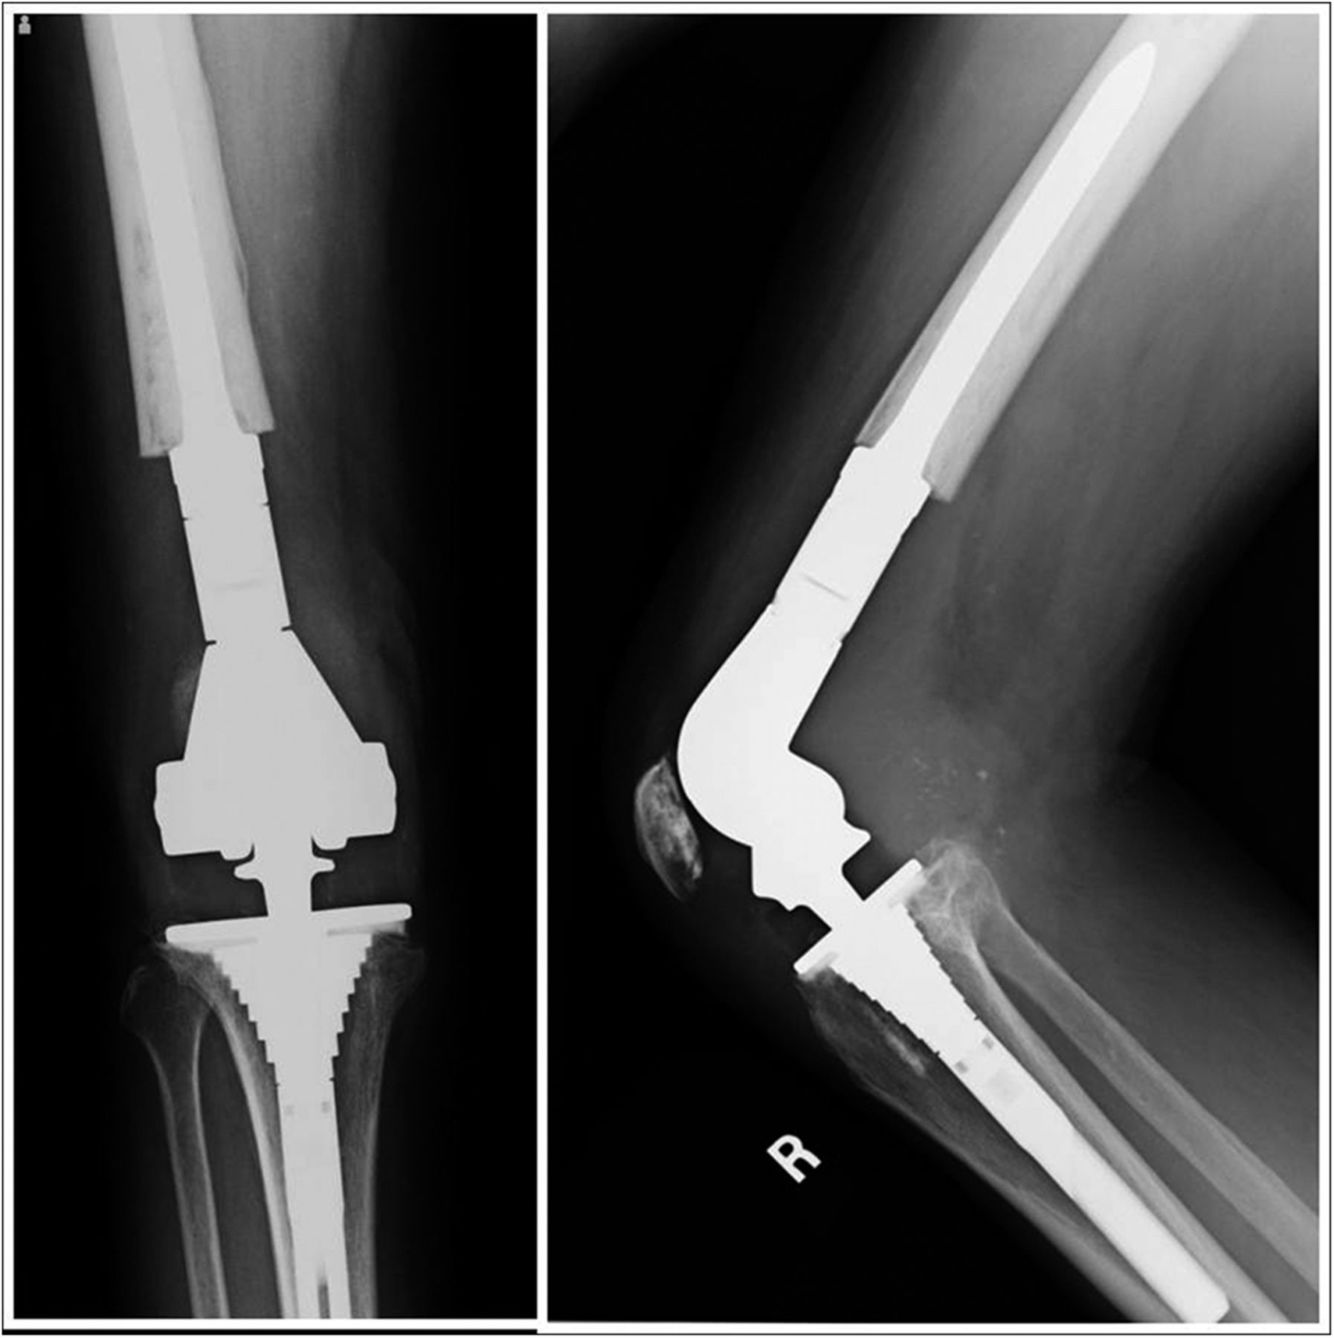

Indications for the following prosthesis

Constrained hinge with rotating platform

Why was this prosthesis choosen?

Tumour Prosthesis